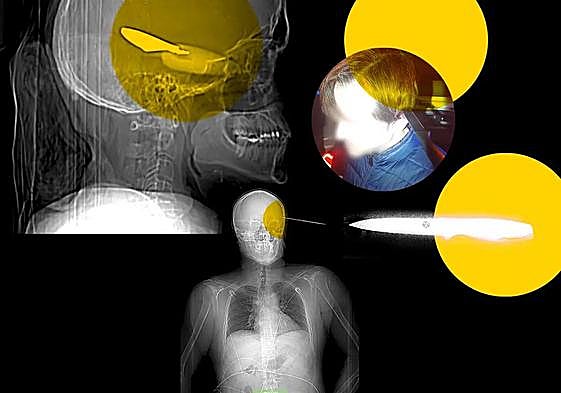

Antonio, el hombre que sobrevivió a un cuchillo incrustado en la cabeza: «Salió a cazar, iba a matarme»

Un menor de 16 años fue detenido en Mijas por apuñalarlo con tal violencia que le dejó el arma blanca clavada en el cráneo